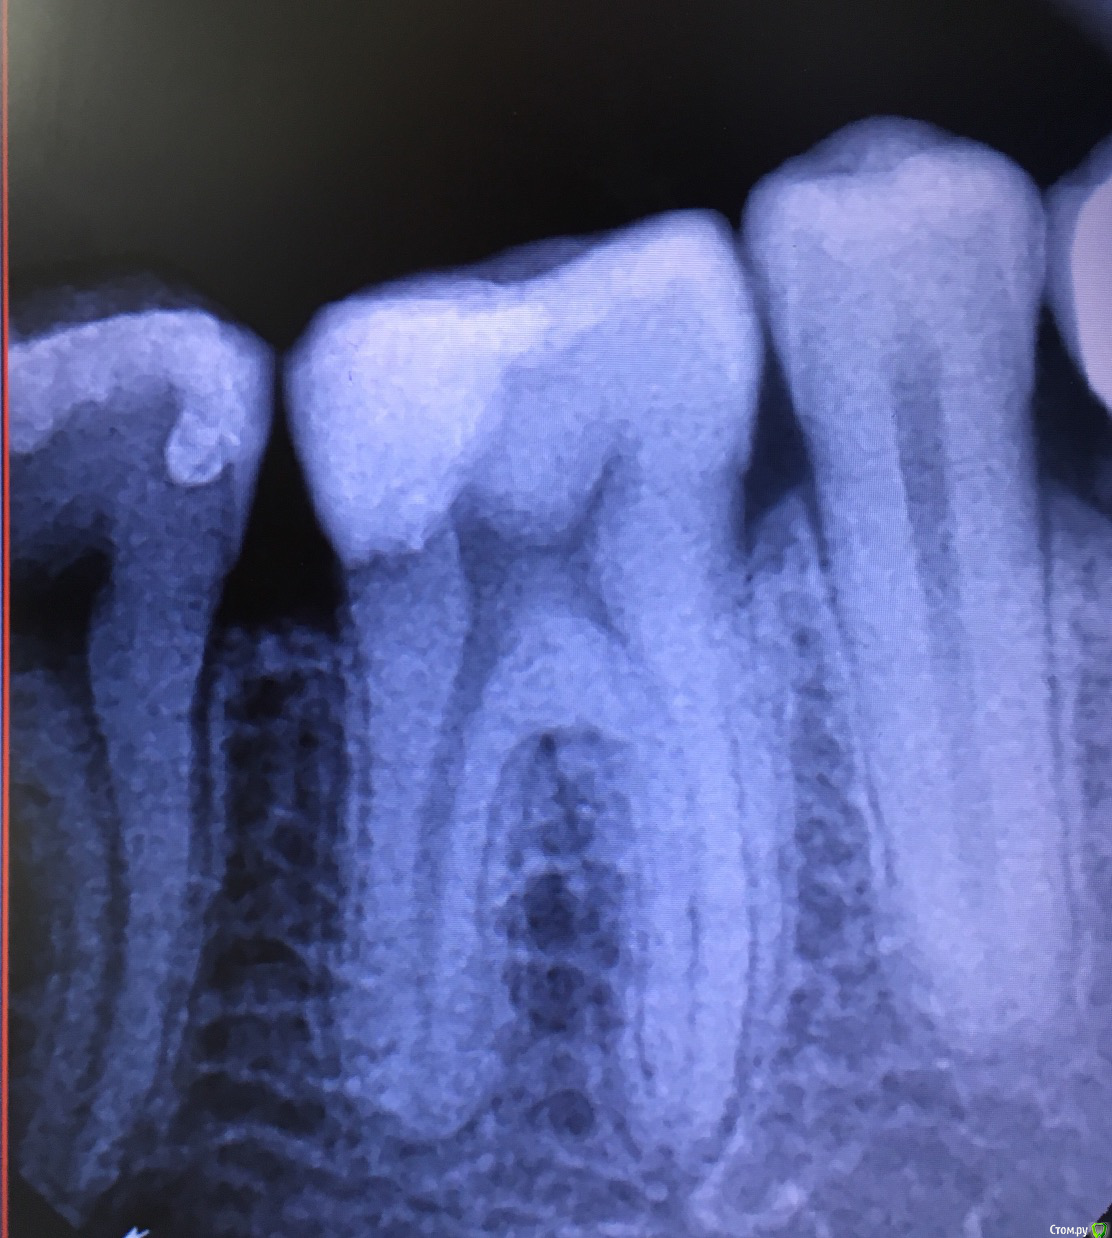

damenic Опубликовано 4 сентября, 2018 Поделиться Опубликовано 4 сентября, 2018 (изменено) Здравствуйте! Недавно разболелся зуб, оказалось большой кариес внутри зуба. Пошел к врачу, сказала, что процесс острый, но пульпу вроде не задело. Поставила пломбу, вечером, когда отошло обезбаливающее, зуб продолжил периодически ныть. На холодное/горячее реагирует, но почти сразу проходит. Болит непостоянно, иногда недолго в течение дня. Пломбу ставили в пятницу, уже вторник, болей стало меньше, но все же есть.Есть ли шанс, что не нужно будет снимать пломбы и удалять нерв? Может ли проблема в неправильной обточке пломбы? Вообщем, можно ли сохранить зуб? Дело в том, что я сейчас в командировке на пару месяцев и вопрос еще, дотяну ли до визита к своему врачу... Изменено 4 сентября, 2018 пользователем damenic Ссылка на комментарий

shishok Опубликовано 4 сентября, 2018 Поделиться Опубликовано 4 сентября, 2018 (изменено) Пломба очень близко к нерву:вероятность,что придется удалять нерв очень большая(если боли будут длительными,самопроизвольными,ночными) Изменено 4 сентября, 2018 пользователем shishok Ссылка на комментарий